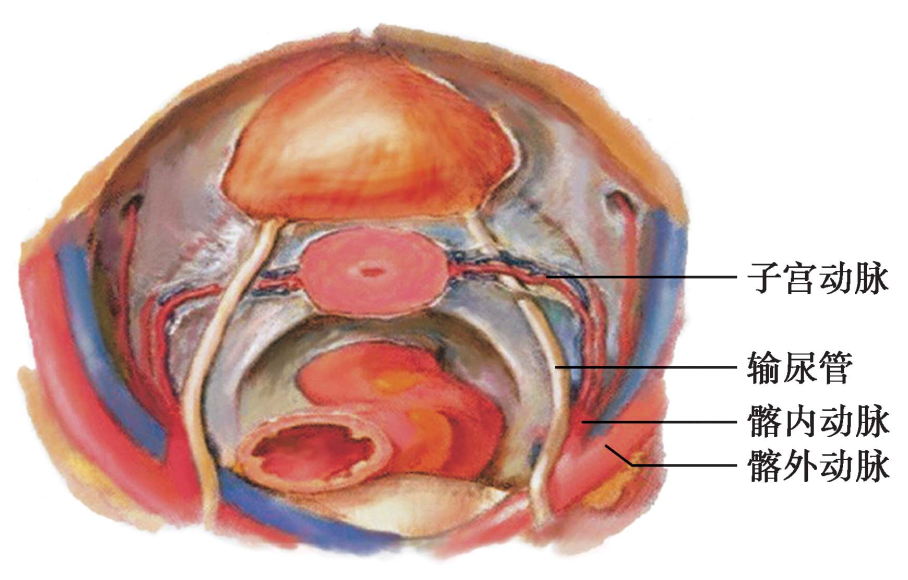

3.输尿管(ureter) 为一对圆索状肌性管道,管壁厚1mm,由黏膜、肌层、外膜构成。全长约30cm,粗细不一,内径最细3~4mm,最粗7~8mm。起自肾盂,在腹膜后沿腰大肌前面偏中线侧下行(腰段);在骶髂关节处跨髂外动脉起点的前方进入骨盆腔(盆段),并继续在腹膜后沿髂内动脉下行,到达阔韧带基底部向前内方行,在子宫颈部外侧约2.0cm,于子宫动脉下方穿过(图2-13),位于子宫颈阴道上部的外侧1.5~2.0cm处,斜向前内穿越输尿管隧道进入膀胱。在施行高位结扎卵巢血管、结扎子宫动脉及打开输尿管隧道时,应避免损伤输尿管。输尿管行程和数目可有变异,且可随子宫发育异常连同该侧肾脏一并缺如。在输尿管走行过程中,支配肾、卵巢、子宫及膀胱的血管在其周围分支并相互吻合,形成丰富的血管丛营养输尿管,在盆腔手术时应注意保护输尿管血运,避免因缺血形成输尿管瘘。

图2-13 输尿管与子宫动脉的关系